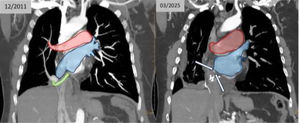

Serial echocardiography demonstrated a progressive increase in estimated systolic pulmonary arterial pressure (from 36mmHg to 54mmHg in 4 years), with indirect signs of PH and no significant intracardiac shunt. Right heart catheterization confirmed PH, with mean pulmonary arterial pressure 34mmHg, pulmonary vascular resistance of 4.5 Wood Unit and pulmonary capillary wedge pressure of 10mmHg (left) and 19mmHg (right), which are findings consistent with group 1 PH [2]. Contrast-enhanced chest CT scan demonstrated the complete occlusion of the right pulmonary venous drainage (Fig. 1).

Contrast-enhanced chest CT scan demonstrating right pulmonary venous drainage correction through pericardial patch (first image) and its complete occlusion (second image). Red: left circulation; Blue: right circulation; Green: pericardial patch conduit connecting to the left atrium via the atrial septal defect.